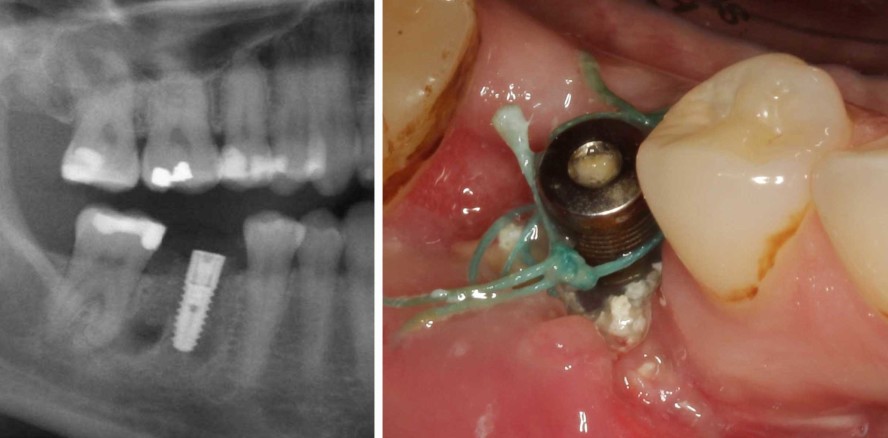

Bei der klinischen Untersuchung zeigte sich, dass das Implantat deutlich supragingival inseriert worden war. Aufgrund des geringen okklusalen Abstands konnte das Implantat nicht prothetisch versorgt werden. Ein großer Teil des Implantatgewindes war sichtbar, einhergehend mit insuffizientem, entzündetem Weichgewebe im OP-Bereich. Nachdem auch die röntgenologische Diagnostik zeigte, dass der Implantaterhalt nicht möglich war, mussten in den folgenden Behandlungsschritten das Implantat und das infizierte Knochenersatzmaterial, das die Heilung verhinderte, entfernt sowie das entstandene Knochendefizit wieder aufgebaut werden (Abb. 2–4).